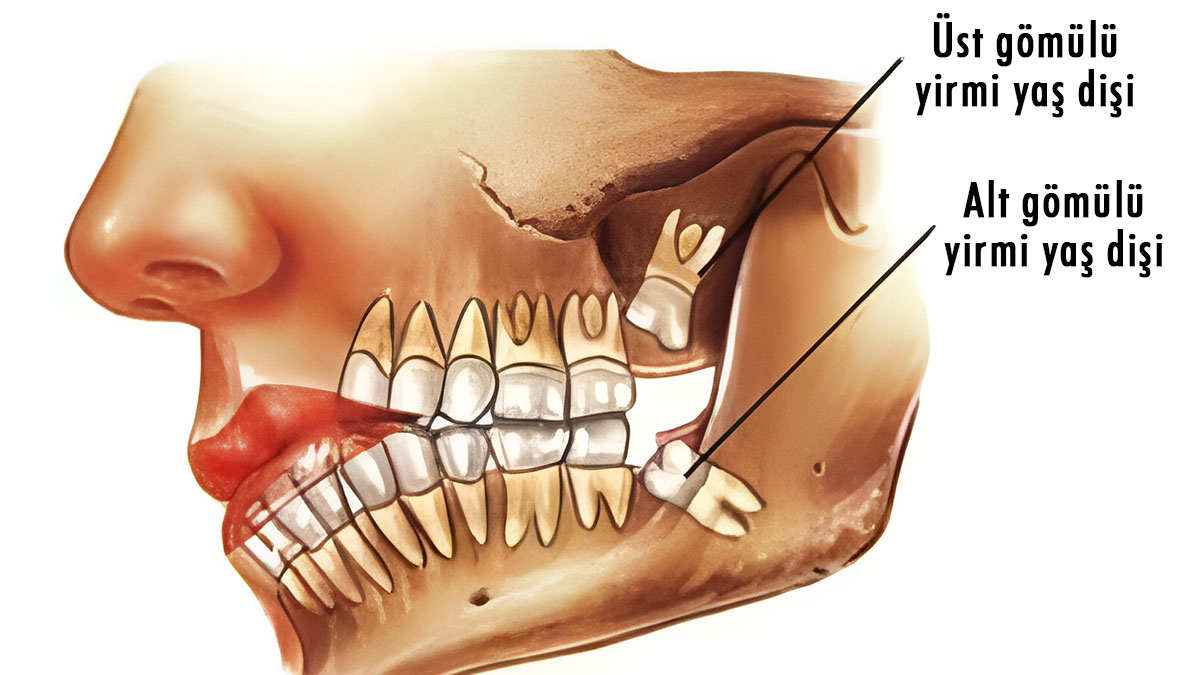

Çenenin küçülmesiyle birlikte, en sonda bulunan yirmilik diş için çenede yeterli yer kalmamaya başladı.

İşte bu adaptasyonun sonucu olarak, günümüzde birçok kişide yirmilik dişler gömülü veya yarı gömülü kalarak çeşitli sağlık sorunlarına yol açmaktadır.

Diş hekimlerinin sıklıkla dile getirdiği, "Çene yapısı dar olduğu için diş çıkmamış, gömülü kalmış" ifadesi, milyonlarca yıllık bu evrimsel süreci özetler niteliktedir.

Yirmilik dişlerin güncel olarak yarattığı başlıca sorunlar arasında ağrı, enfeksiyon (perikoronitis), diş eti iltihabı, kist oluşumu ve komşu dişlere baskı yaparak çapraşıklığa yol açması yer alır.

Özellikle tam çıkamayan veya yanlış pozisyonda sürmeye çalışan gömülü dişler, çevrelerindeki kemik ve yumuşak dokuya zarar verebilir.